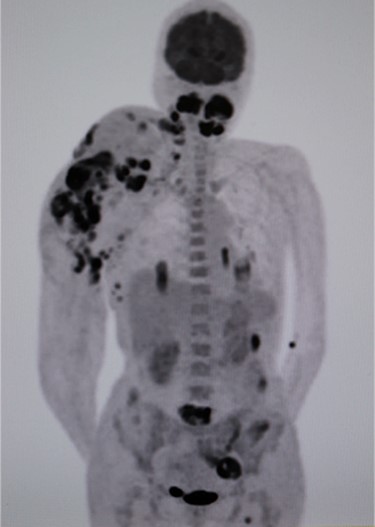

Positron emission tomography–computed tomography (CT) revealed high fluorodeoxyglucose (FDG) accumulation in her oral cavity and right shoulder in accordance with the location of the AVM (Fig. 4). High accumulation was also evident in her left lung, lumbar spine, piriformis and lymph nodes, suggesting multiple metastases. We diagnosed the masses in the oral cavity as metastatic AS, with the primary tumour located in the right shoulder, where the massive AVM was suspected to have malignantly transformed. The patient desired the best supportive care and declined additional treatments such as radiotherapy and chemotherapy. She died 4 months after initially noticing the intraoral masses. An autopsy was not performed.

Positron emission tomography–computed tomography (PET-CT). High fluorodeoxyglucose (FDG) accumulation in the oral cavity as well as in the right shoulder where the AVM was located. High accumulation was also evident in the left lung, lumbar spine, piriformis and lymph nodes.

AS is an aggressive malignant tumour with high metastatic potential. Main metastatic sites of AS include the lungs (25%), bone (22%), liver (16%) and brain (11%) (3). Intraoral metastatic AS is rare but tends to localize in the gingiva (4). As is often the case with oral metastases from other primary lesions, their presence is evidence of widespread disease. Although we could not identify the primary lesion in the right shoulder by visual inspection or CT scan due to the massive AVM, we considered it highly unlikely that the masses in the oral cavity formed the primary lesion. Only a few studies have reported on primary intraoral AS with multiple lesions, and the widest range of high FDG accumulation in our case was observed in the right shoulder.

In our case, the location of the primary lesion could not be clarified given the existence of multiple metastases at the time of diagnosis. However, it is reasonable to speculate that AS arose from the shoulder AVM, where the widest range of FDG accumulation was observed. Careful monitoring of AS occurrence is needed in patients with vascular malformation, particularly those with risk factors such as a history of radiation therapy and immunosuppression.